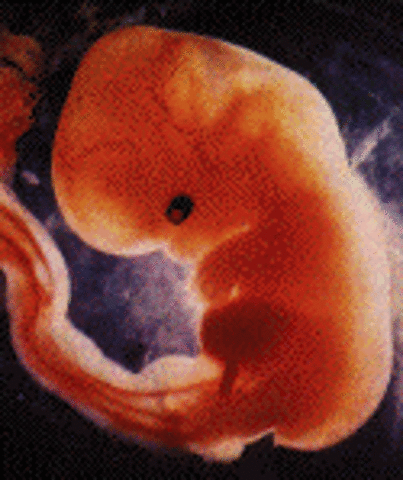

• Week 5: The Embryonic Stage Begins

Week 5: The Embryonic Stage Begins

In this stage, the placenta is beginning to form. The embryo will double in size from the week 4 embryo by the edn of week 5.